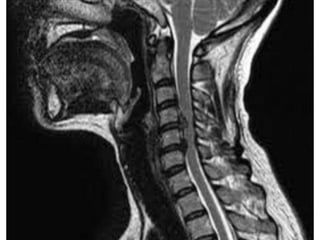

Note:the black line directly posterior to the vertebral bodies and relative

Thinning of spinal cord, note normal disc height

Mid-sagittal diameter: width

1:5 ratio leads to necrosis of gray

matter

• Ogino H: Canal diameter, anteroposterior compression ratio

and spondylotic myelopathy of the cervical spine. Spine 1983;

8:1-15

• Cord compression causes ischemia and direct mechanical

trauma

Note:the black linedirectly posterior to the vertebral bodies and relative Thinning of spinal cord, note normal disc height

Mid-sagittal diameter: width 1:5ratio leads to necrosis of gray matter • Ogino H: Canal diameter, anteroposterior compression ratio and spondylotic myelopathy of the cervical spine. Spine 1983; 8:1-15 • Cord compression causes ischemia and direct mechanical trauma